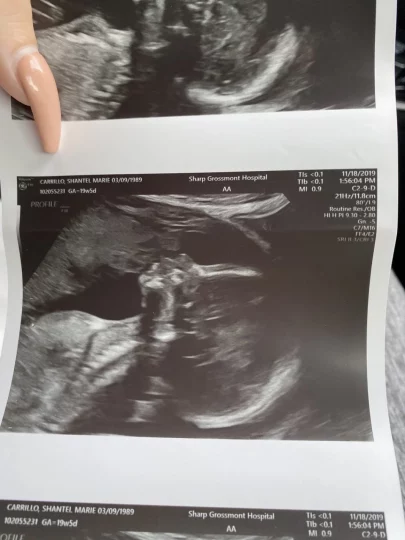

Quando uma mãe grávida de San Diego visitou o consultório de seu médico para um ultrassom, ela esperava ter um vislumbre de sua futura filha. O que ela viu foi isso, e também algo mais: um olhar para o seu passado.

Shantel Carrillo, de 30 anos, a mãe em questão foi para sua consulta de ultrassom de rotina, conforme informações do portal de notícias NBC. Tudo parecia normal, apenas sua filha dentro da barriga que não ficava parada por tempo suficiente para que pudessem tirar uma foto.

Carrillo realmente queria ver o rosto de seu bebê, mas um perfil lateral era o melhor que a técnica podia fazer.

Ela e seu parceiro, Bryce Vinson, ficaram tão felizes em ver o rosto do bebê que realmente não notaram mais nada na imagem do ultrassom.

Foi só quando Shantel publicou as fotos do ultrassom em suas redes sociais que um ponto da imagem começou a se destacar.

Seus amigos e familiares não viram apenas o rosto do bebê. Eles viram o rosto do falecido pai de Shantel!

A mulher se recorda que menos de um minuto depois de postar a foto, alguém comentou na publicação que havia um anjo beijando seu bebê!

Carrillo disse que a imagem de seu pai estava no canto superior esquerdo do ultrassom. Ela disse à NBC que parecia que seu pai estava se inclinando sobre seu bebê, beijando seu rostinho, bem nos lábios.

Ela não conseguia acreditar, mas realmente, parecia seu pai na imagem. Shantel enviou a foto para seus familiares mais próximos e eles concordaram.

Carrillo decidiu postar a imagem em outra rede social também, o Reddit, e logo o close-up de seu bebê se tornou viral.

Com isso, veio muita atenção e, naturalmente, muitos pessimistas. A mãe disse que muitas pessoas online a acusaram de usar o Photoshop para alterar o ultrassom, mas ela insistiu que não é o caso e que ela jamais faria isso.

Carrillo disse que ela mesma não tem certeza do que está na foto ou por que está lá, mas pensar naquela imagem, na semelhança do pai olhando para o bebê, era muito reconfortante para ela.

Carrillo disse que o ultrassom se assemelha a uma foto de seu pai beijando sua filha mais velha, 10 anos antes deste ocorrido. Nessa foto, ele está inclinado, olhando carinhosamente para o bebê e sorrindo. Ele está usando um chapéu – algo que ele fazia com frequência.

No ultrassom, Carrillo disse que também parecia que seu pai estava de chapéu.